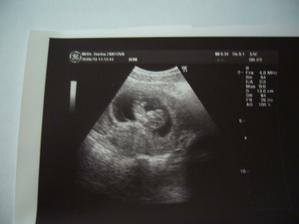

30.6. mimčo krásně vyrostlo a jsme objednaný na NT screening.

14.7. NT screening dopadl dobře. Tak se mi ulevilo.

22.7. KO vše v pořádku. Mimčo nám ukázalo záda:o) už nám takhle brzo dává najevo co si o nás myslí:o)